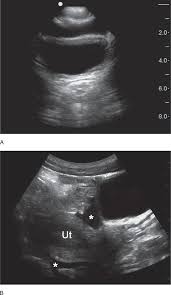

Free fluid in the Pouch of Douglas is a common finding during medical imaging. This simply means that there is a small amount of fluid in the space between your uterus and rectum. In most cases, free fluid in the Pouch of Douglas is harmless and doesn’t require any treatment. It can be caused by a number of things, including:

Normal menstrual cycles: A little bit of fluid is normal during your period.

Ovulation: Fluid can also accumulate in this area during ovulation.

Pregnancy: Fluid is common during pregnancy, especially in the later stages.

However, free fluid in the Pouch of Douglas can sometimes be a sign of a more serious condition, like:

Pelvic inflammatory disease (PID): This is an infection of the reproductive organs.

Ectopic pregnancy: This is a pregnancy that occurs outside the uterus.

Endometriosis: This is a condition where tissue similar to the lining of the uterus grows outside the uterus.

If you are concerned about free fluid in the Pouch of Douglas, it is important to talk to your doctor. They can help determine the cause of the fluid and recommend the appropriate treatment, if necessary.

Don’t worry, most cases of free fluid in the Pouch of Douglas are benign and don’t require treatment. However, it’s always best to talk to your doctor if you have any concerns. They can help you understand what’s going on and put your mind at ease.